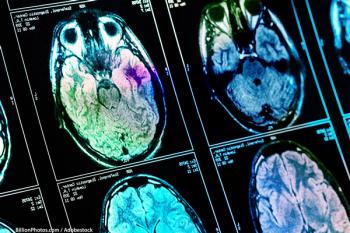

Brain Cancer